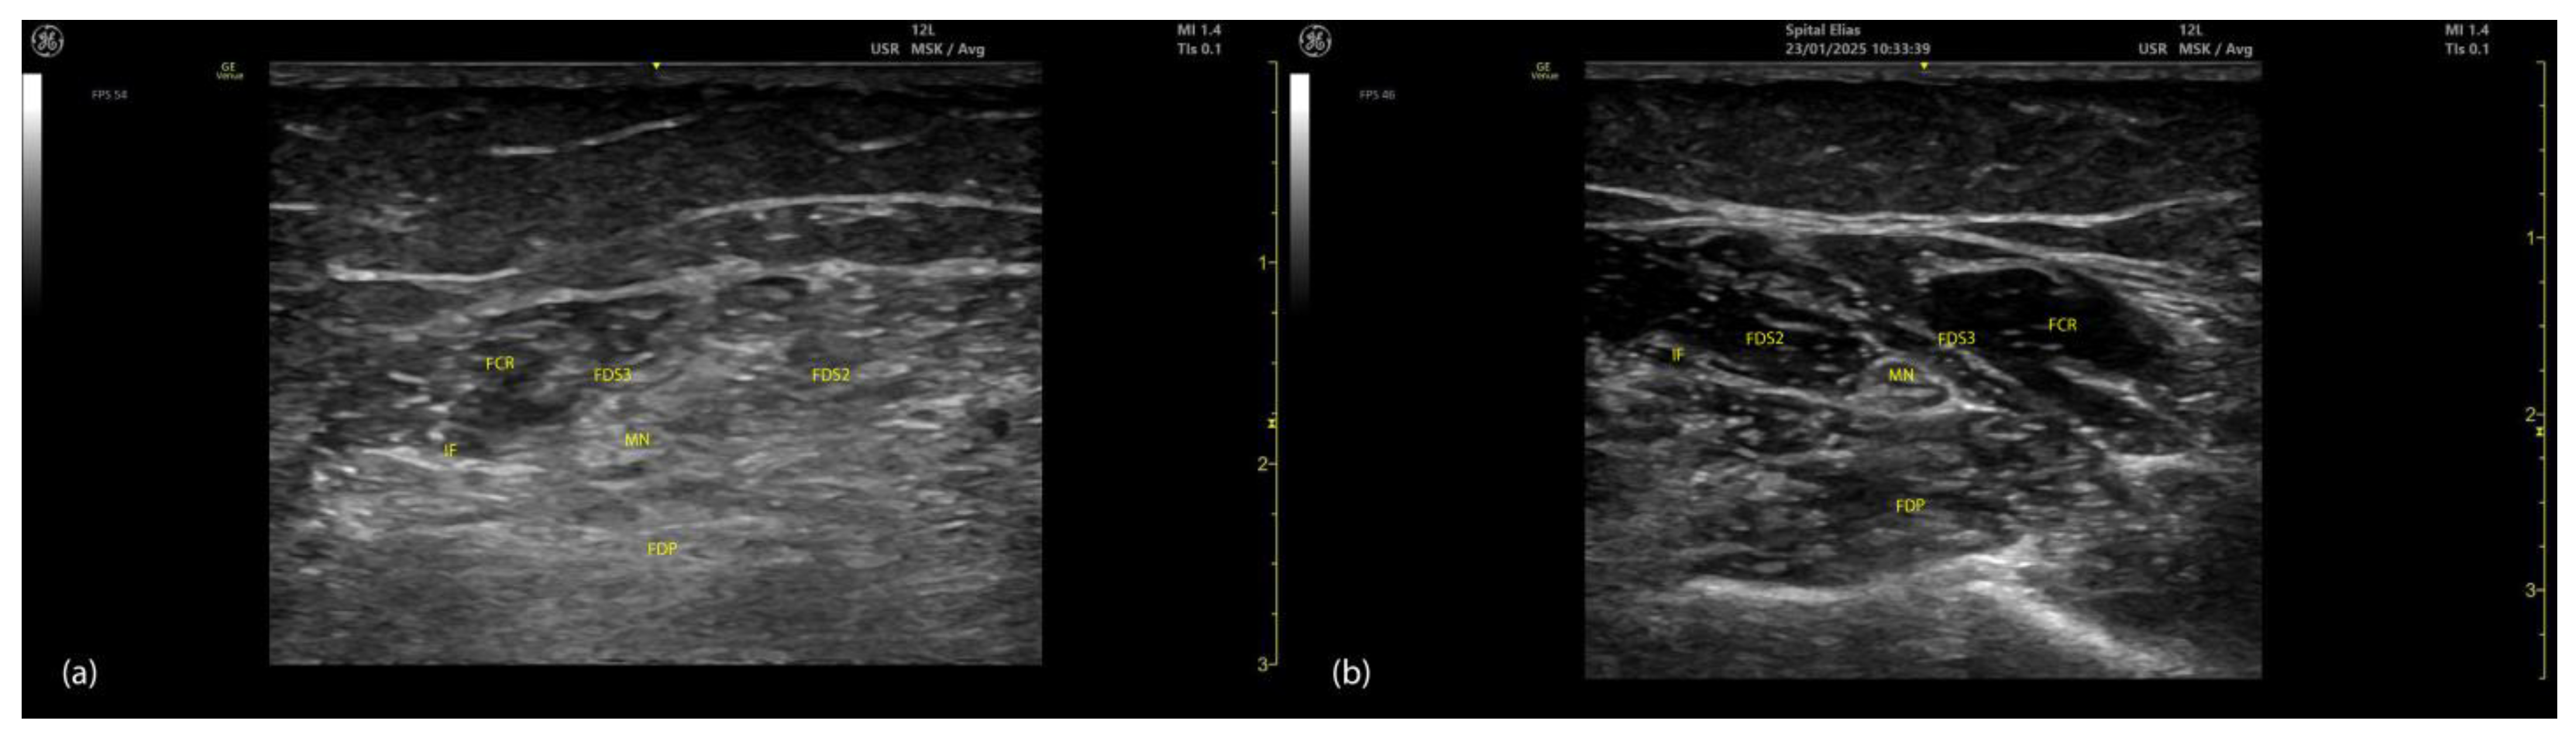

2.4.3. Key Ultrasound Landmarks (Figure 4 and Figure 5)

- Muscle position: At the mid-forearm, the FDS represents the second muscle mass from the cortical surfaces of the radius and ulna, moving from deep to superficial. Superficial to the FDS are the lateral FCR and medial FCU [29]. In the absence of US guidance, these adjacent muscles may be mistaken for the FDS, increasing the risk of injection errors.

- Median nerve: The median nerve is adhered to the deep surface of the FDS. At this level, the FDS and FDP are separated by the intermuscular fascia, which houses the median nerve, ulnar nerve, and ulnar artery [26].

- External fascia: FDS2 and FDS3 have a pronounced external fascia that distinctly demarcates them from adjacent muscle masses during BoNT-A injections, whereas FDS4 and FDS5 lack this feature.

- Dynamic evaluation (Video S3): The contraction of FDS muscle bellies corresponding to fingers II–V is observed during flexion of the metacarpophalangeal and proximal interphalangeal joints. A paradoxical arrangement of FDS2 and FDS3 bellies can be noted anatomically, as they appear inversely positioned medially and laterally relative to the median nerve [30]. Dynamic scanning proximal to the medial epicondyle reveals that the maximal thickness of FDS4 is located approximately 2–3 cm distal to the elbow crease, on the volar aspect of the forearm in the ulnar portion. At this level, the FDS4 is situated medial to the FCR and lateral to the FCU, following the line connecting the medial epicondyle to the pisiform bone [31]. A potential source of error in targeting FDS4 at this level is the palmaris longus (PL) muscle, which, if present, is located between the FCR and FDS4 muscle bellies. The PL is variably present in 74–97.5% of the population and is most commonly bilateral [32,33].

2.5.3. Key Ultrasound Landmarks (Figure 4 and Figure 5)

- Muscle position: At the mid-forearm, the FDP is the first muscle mass located directly superficial to the cortical surfaces of the radius and ulna [29].

- Intermuscular fascia: The FDP is separated from the FDS by intermuscular fascia that houses the median nerve, ulnar nerve, and ulnar artery [31].

- Median nerve: The median nerve adheres to the deep surface of the FDS and is positioned superficially relative to the FDP at this level [31].

- Internal fascia: FDP 2–5 is a single continuous muscle with four distinct tendons, corresponding to digits 2–5. Unlike some other muscles, the FDP does not have a pronounced fascia that demarcates separate muscle masses for each individual finger, making it a continuous muscular structure without clear fascial boundaries for each digit during BoNT-A injection.